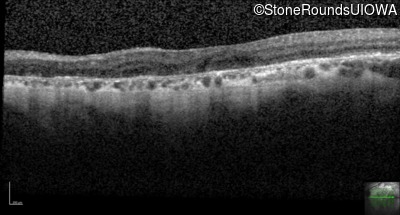

Foveal Hypoplasia (IIIG)

Highlighted Images

Diagnosis & molecular findings

Foveal Hypoplasia PAX6 Pro76Leu CCG>CTG   AD